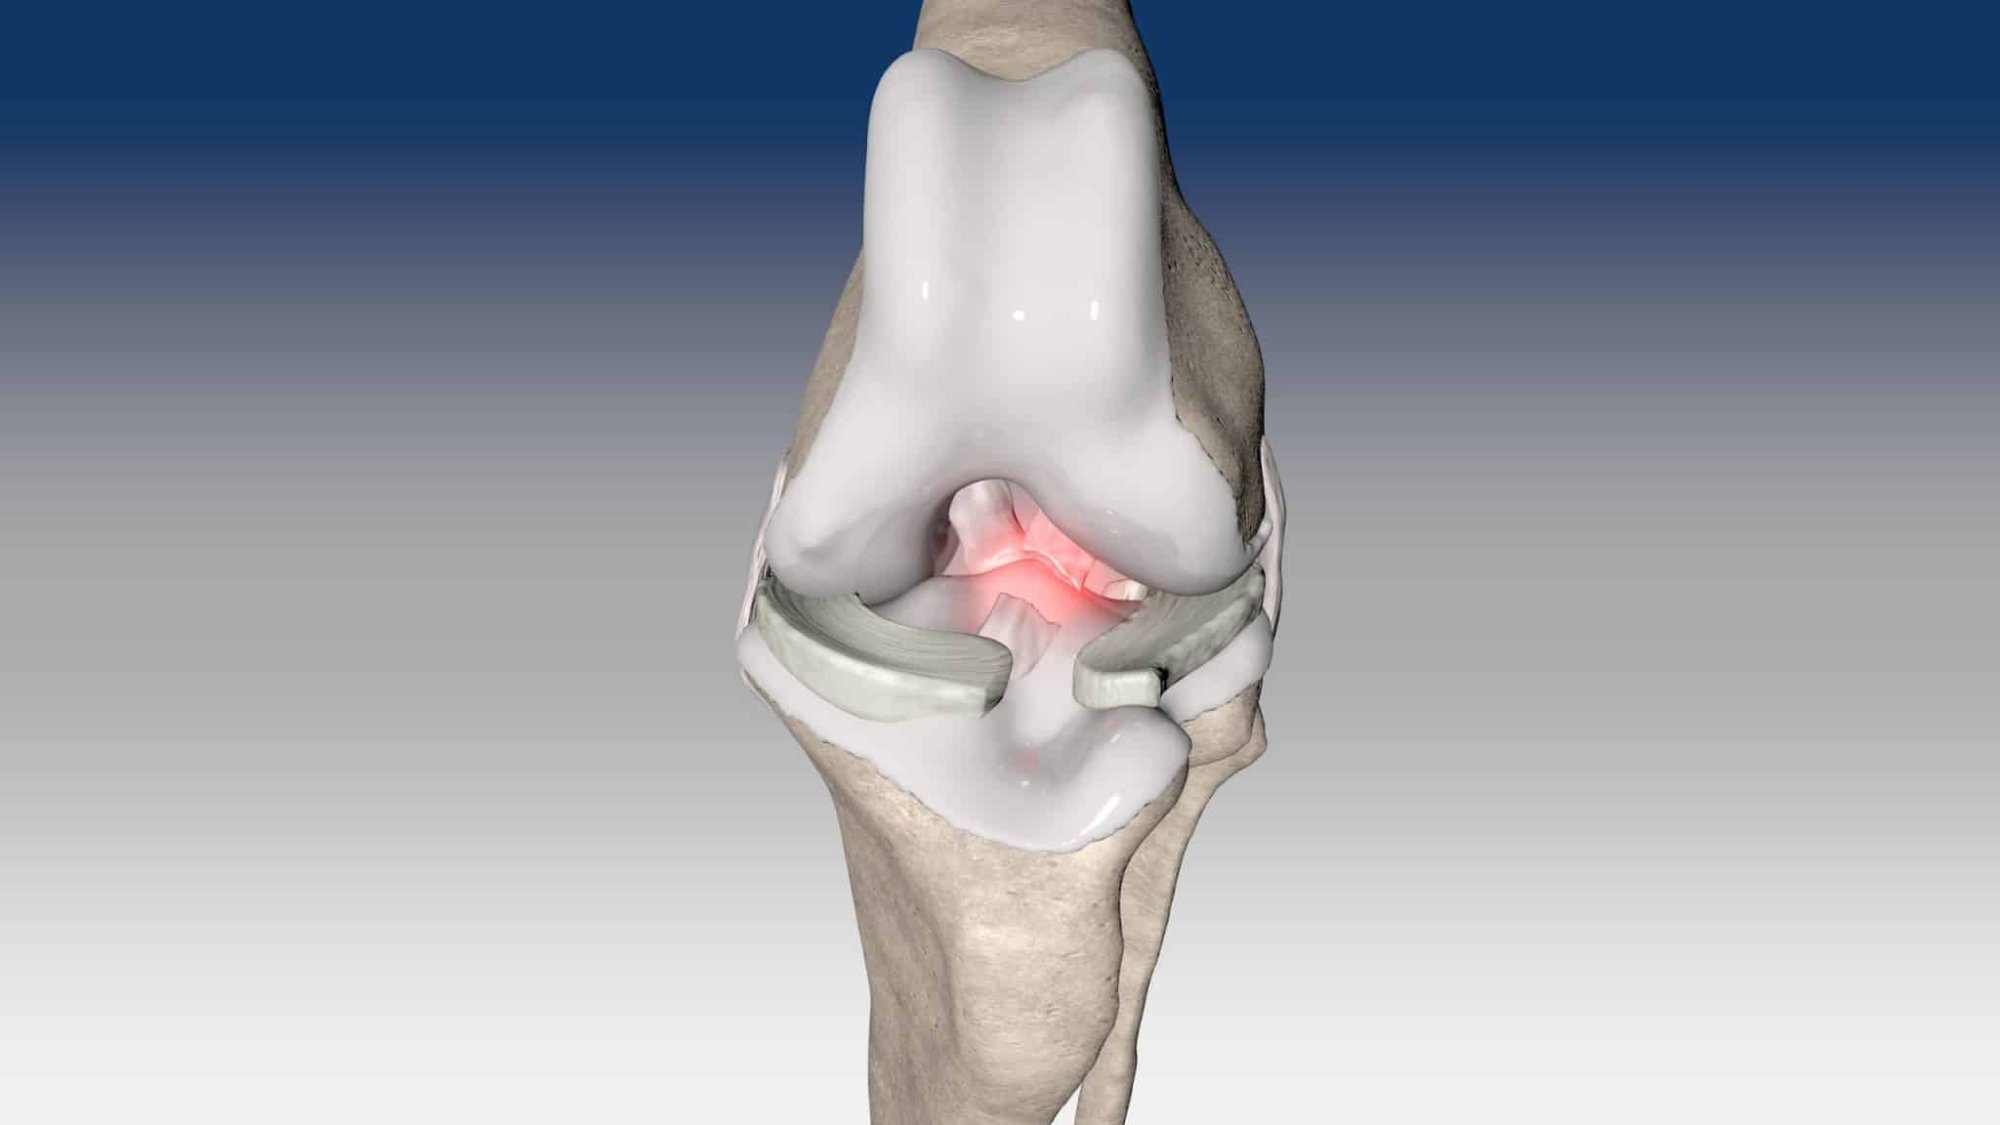

Ruptura kraniálního zkříženého vazu je hlavní příčinou ortopedických konzultací u psů. Tento stav se obvykle léčí chirurgicky pomocí osteotomických technik, mimokloubní stabilizace nebo intraartikulární rekonstrukce.

V případě ruptury kraniálního zkříženého vazu umožňuje ExtraTape® extraartikulární rekonstrukci co nejblíže izometrii původního vazu, čímž rychle a trvale stabilizuje koleno bez uzlů a zvlnění, což je slabina tradičnějších technik extraartikulární stabilizace. Ty jsou zde nahrazeny pevným ukotvením kosti pomocí interferenčního šroubu.

Řešení, které respektuje původní anatomii, obnovuje funkci postiženého vazu a je dostupné v rámci otevřené nebo artroskopické chirurgie.

V případě zkřížených vazů umožňuje intraartikulární rekonstrukci v izometrických bodech připojení, čímž obnovuje biomechaniku kolene a všechny funkce natrženého vazu.